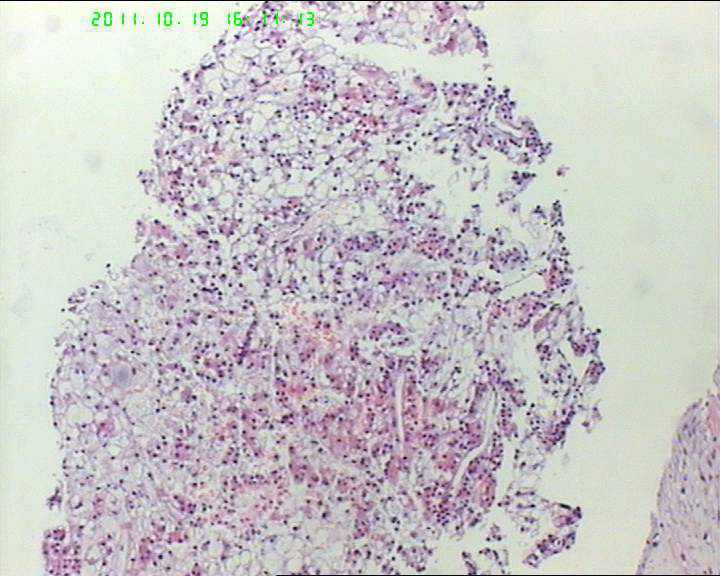

• 71岁男性肝脏占位,ct示低密灶,大三阳,afp高,转氨酶略高。该诊断什么呢?图3

图3